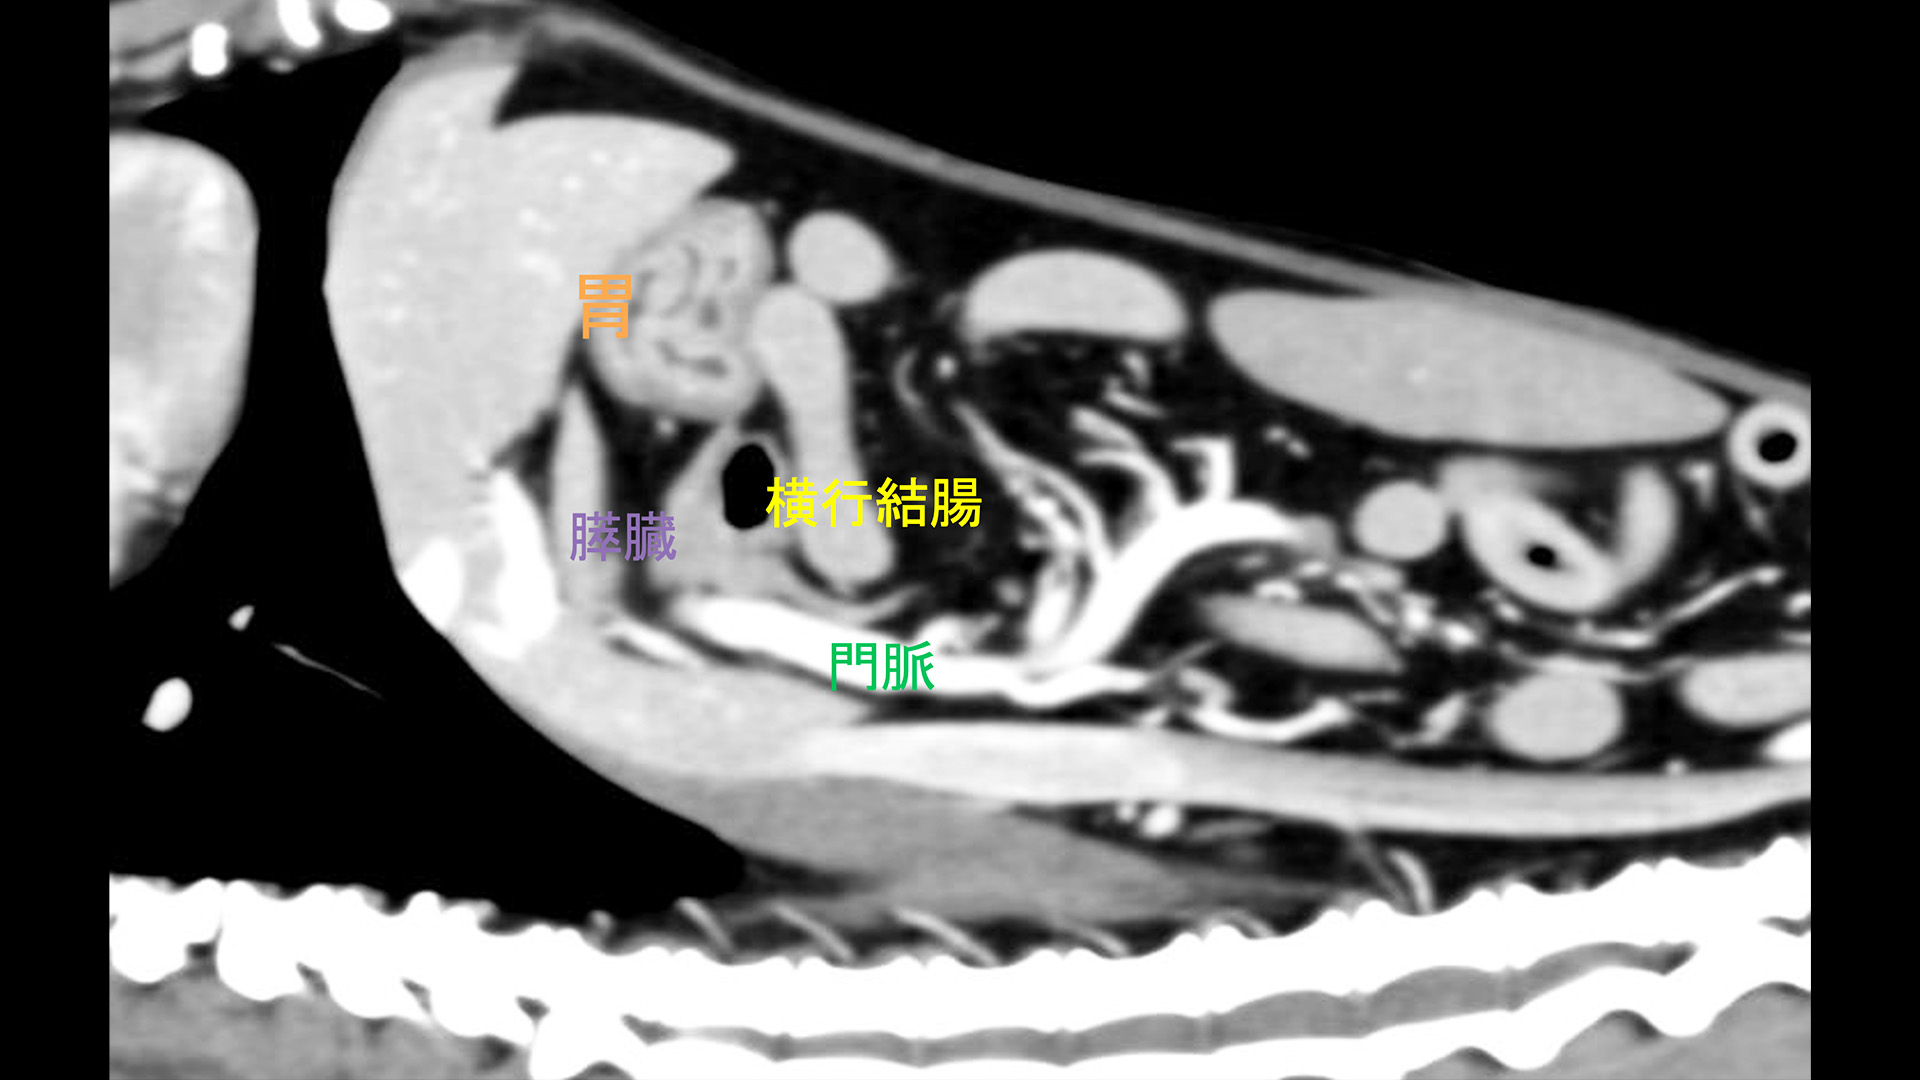

膵臓は、胃と小腸の後ろに位置する体内の臓器です。その機能の 1 つは、腸内で食物の消化を助ける酵素を生成することです。これらの酵素は、消化液の形で膵臓から膵管を通って小腸の上部に放出されます。

膵臓分裂は、出生時から存在する膵臓の最も一般的な異常です。通常、すべてのヒトの胎児は、腹側管と背側管という独自の管を備えた 2 つの部分に分かれた膵臓で生命を開始します。通常、開発中にこれら 2 つの部分が融合し、2 つのダクトも融合して 1 つのダクトになります。膵臓分裂では、発生中に管が融合せず、膵臓に 2 つの別々の管が残った状態になります。